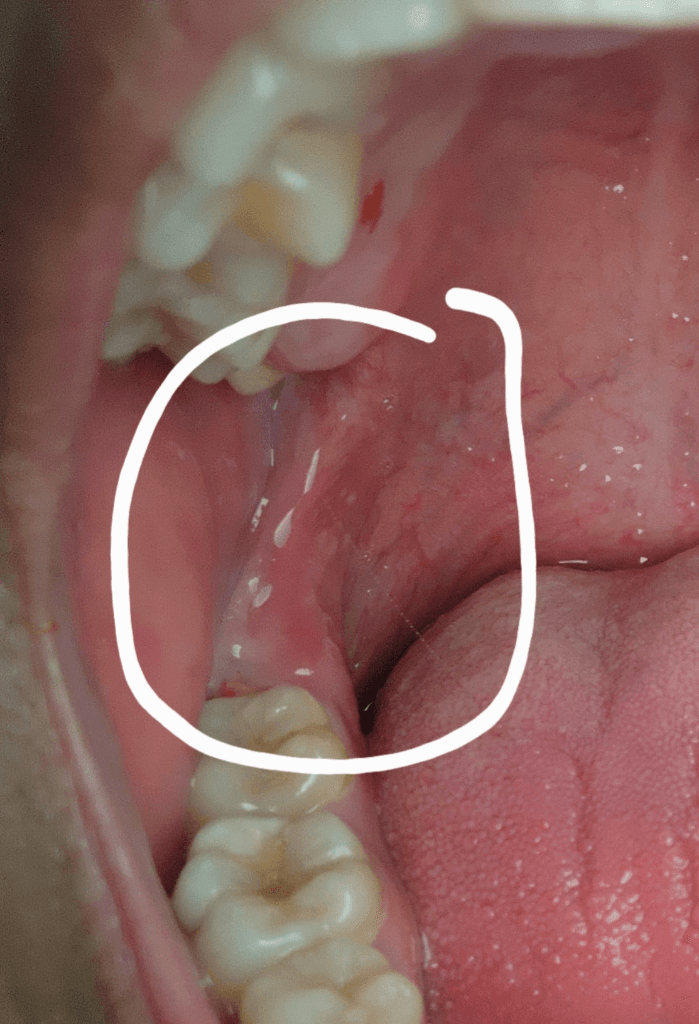

이틀전부터 잇몸 연결부위 쪽이 아파서 살펴봤더니..

이틀전부터 잇몸 연결부위(저 쪽을 뭐라 부르는지

모르겠습니다)쪽이 밥을 먹거나 입을 다물때마다

씹히고 아파서 살펴보니 살짝 부은 것 같습니다..

만지면 아픈데 자연치유가 될까요?아니면 약을 먹어야

할까요??

• 1번 째 사진

정확한 것은 검사를 해보아야겠지만 일시적으로 해당 부위에 치아가 닿아서 상처가 생긴 경우라면 수 일 이내에 회복되는 특성을 보입니다. 다만 현재 사진만으로는 정확한 원인 파악이 어려우며 2~3일이 지나도 증상이 호전되지 않는다면 가까운 치과 방문 후 평가를 해보는 것이 필요합니다.

구내염 증상이 있는 것으로 보이며, 크게 문제가 되지는 않습니다. 통증이 있는 경우 약국에서 소염진통제를 구매하여 복용을 하고, 소염진통성분의 가글액 사용이 증상을 가라앉히는데 도움이 됩니다.

사진상으로 보면 지금도 가장 뒷치아 잇몸쪽에 음식물이 껴잇는것처럼 보이고 구내염도 잇어 보입니다. 치과에 가셔서 검진을 받아보세요.

1. 해당부위는 구후융기로 부위입니다.

2. 해당 부위 염증상태로 보이나 일시적인 증상이고 1~2주 내로 호전될 것으로 보입니다